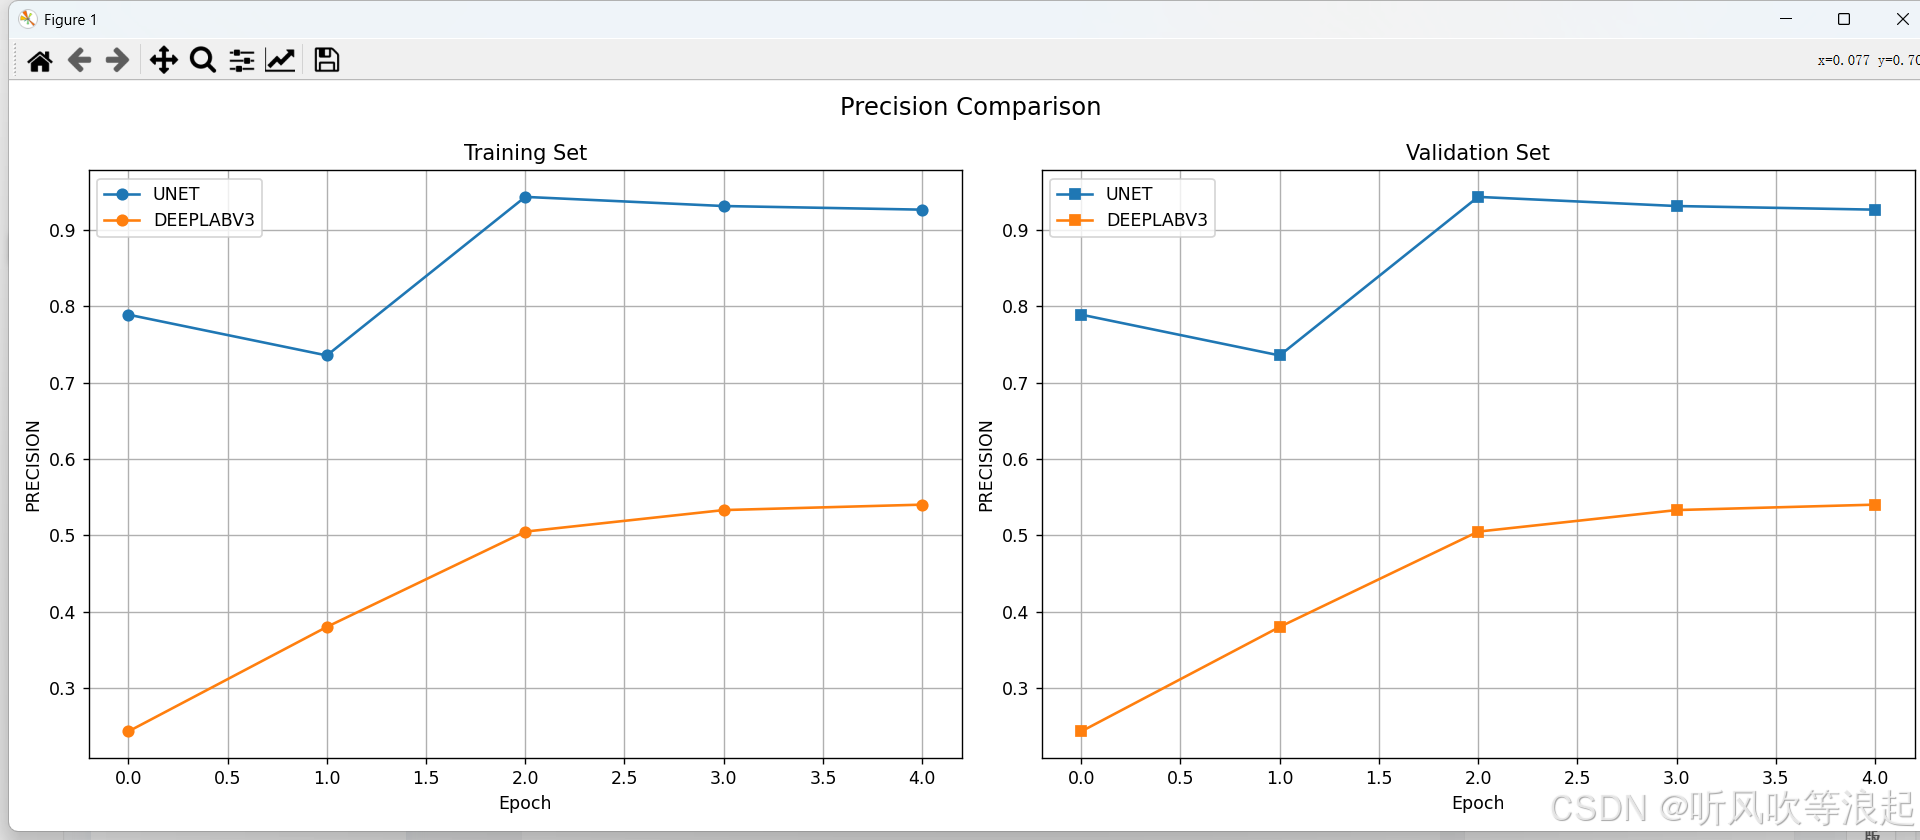

通过可视化工具可以直观比较不同模型的性能表现:

ax2.plot(epochs, values, label=model_name.upper())可视化结果通常显示:

- UNet在小数据集上通常收敛更快

- DeepLabV3在大数据集上表现更优

- 两种模型在不同指标上的曲线

这里仅仅训练了5个epoch用于测试代码的可行性,指标不做参考

3.对比